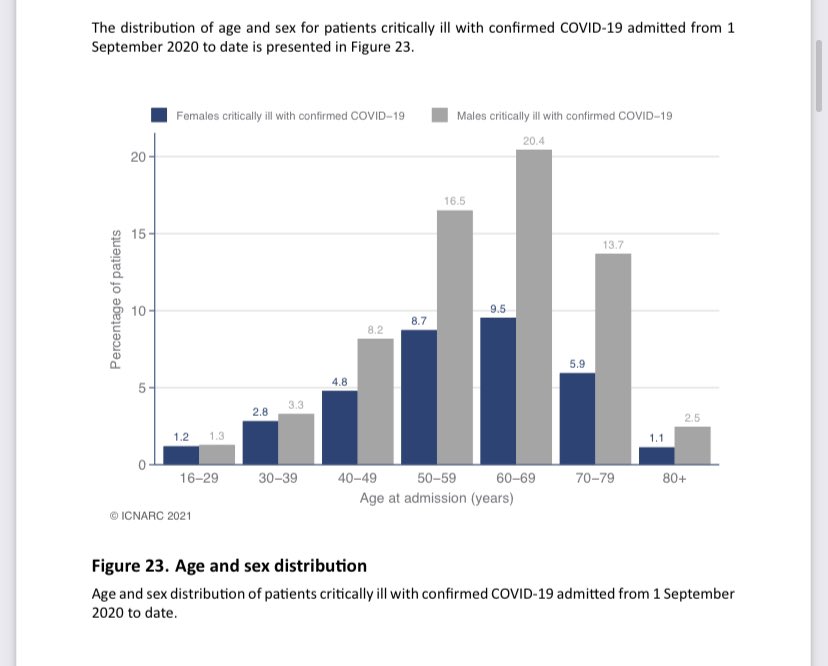

2/ Between 5-10% of ICU patients are 20-40 years old - https://www.icnarc.org/DataServices/Attachments/Download/2d288f8e-728e-eb11-912f-00505601089b

And">https://www.icnarc.org/DataServi... frontline healthcare workers are over represented compared to the general population.

And">https://www.icnarc.org/DataServi... frontline healthcare workers are over represented compared to the general population.